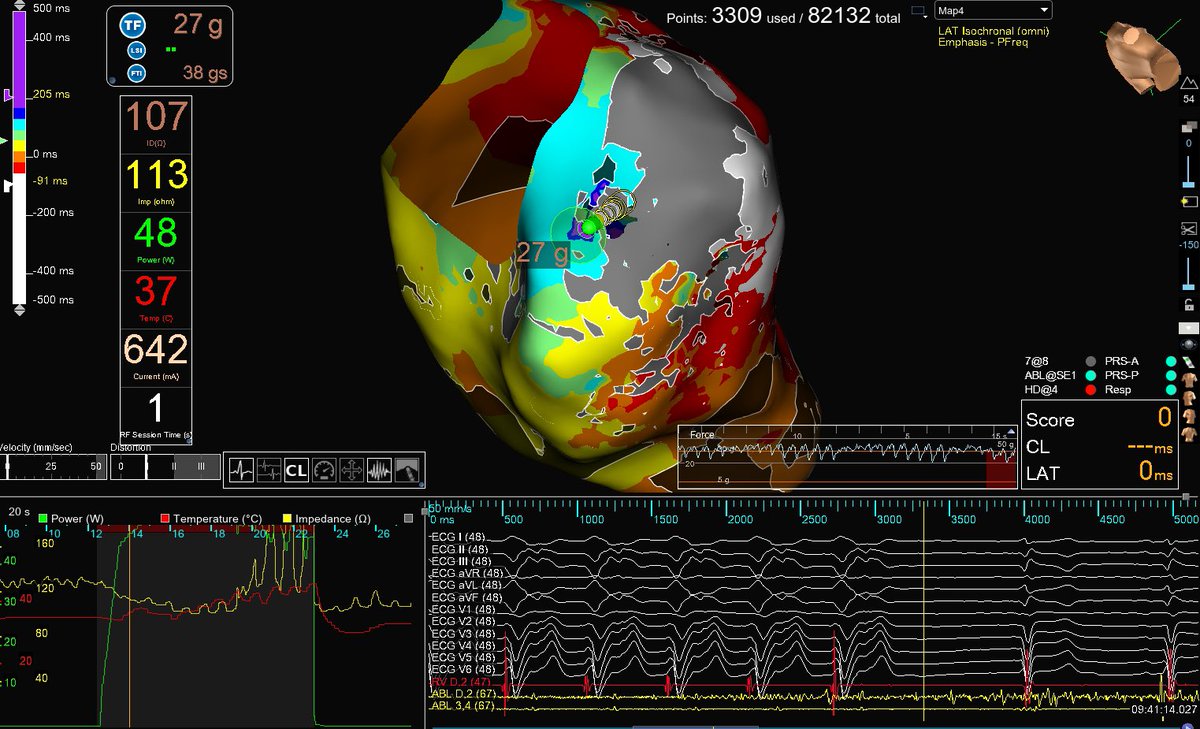

Beautiful Ischemic VT ablation mapped and ablated by Jalaj Garg utilizing #HDGrid. One-burn term achieved, utilizing 1. #EnsiteX nearfield detection algorithm with #Emphasismaps 2. #ILAM map achieved in VT with #lastdetection algorithm. #AbbottProud #OT Abbott Cardiovascular

Beautiful Ischemic VT ablation mapped and ablated by <a href="/drjalajgarg/">Jalaj Garg</a> utilizing #HDGrid. One-burn term achieved, utilizing

1. #EnsiteX nearfield detection algorithm with #Emphasismaps

2. #ILAM map achieved in VT with #lastdetection algorithm.

#AbbottProud #OT <a href="/AbbottCardio/">Abbott Cardiovascular</a>